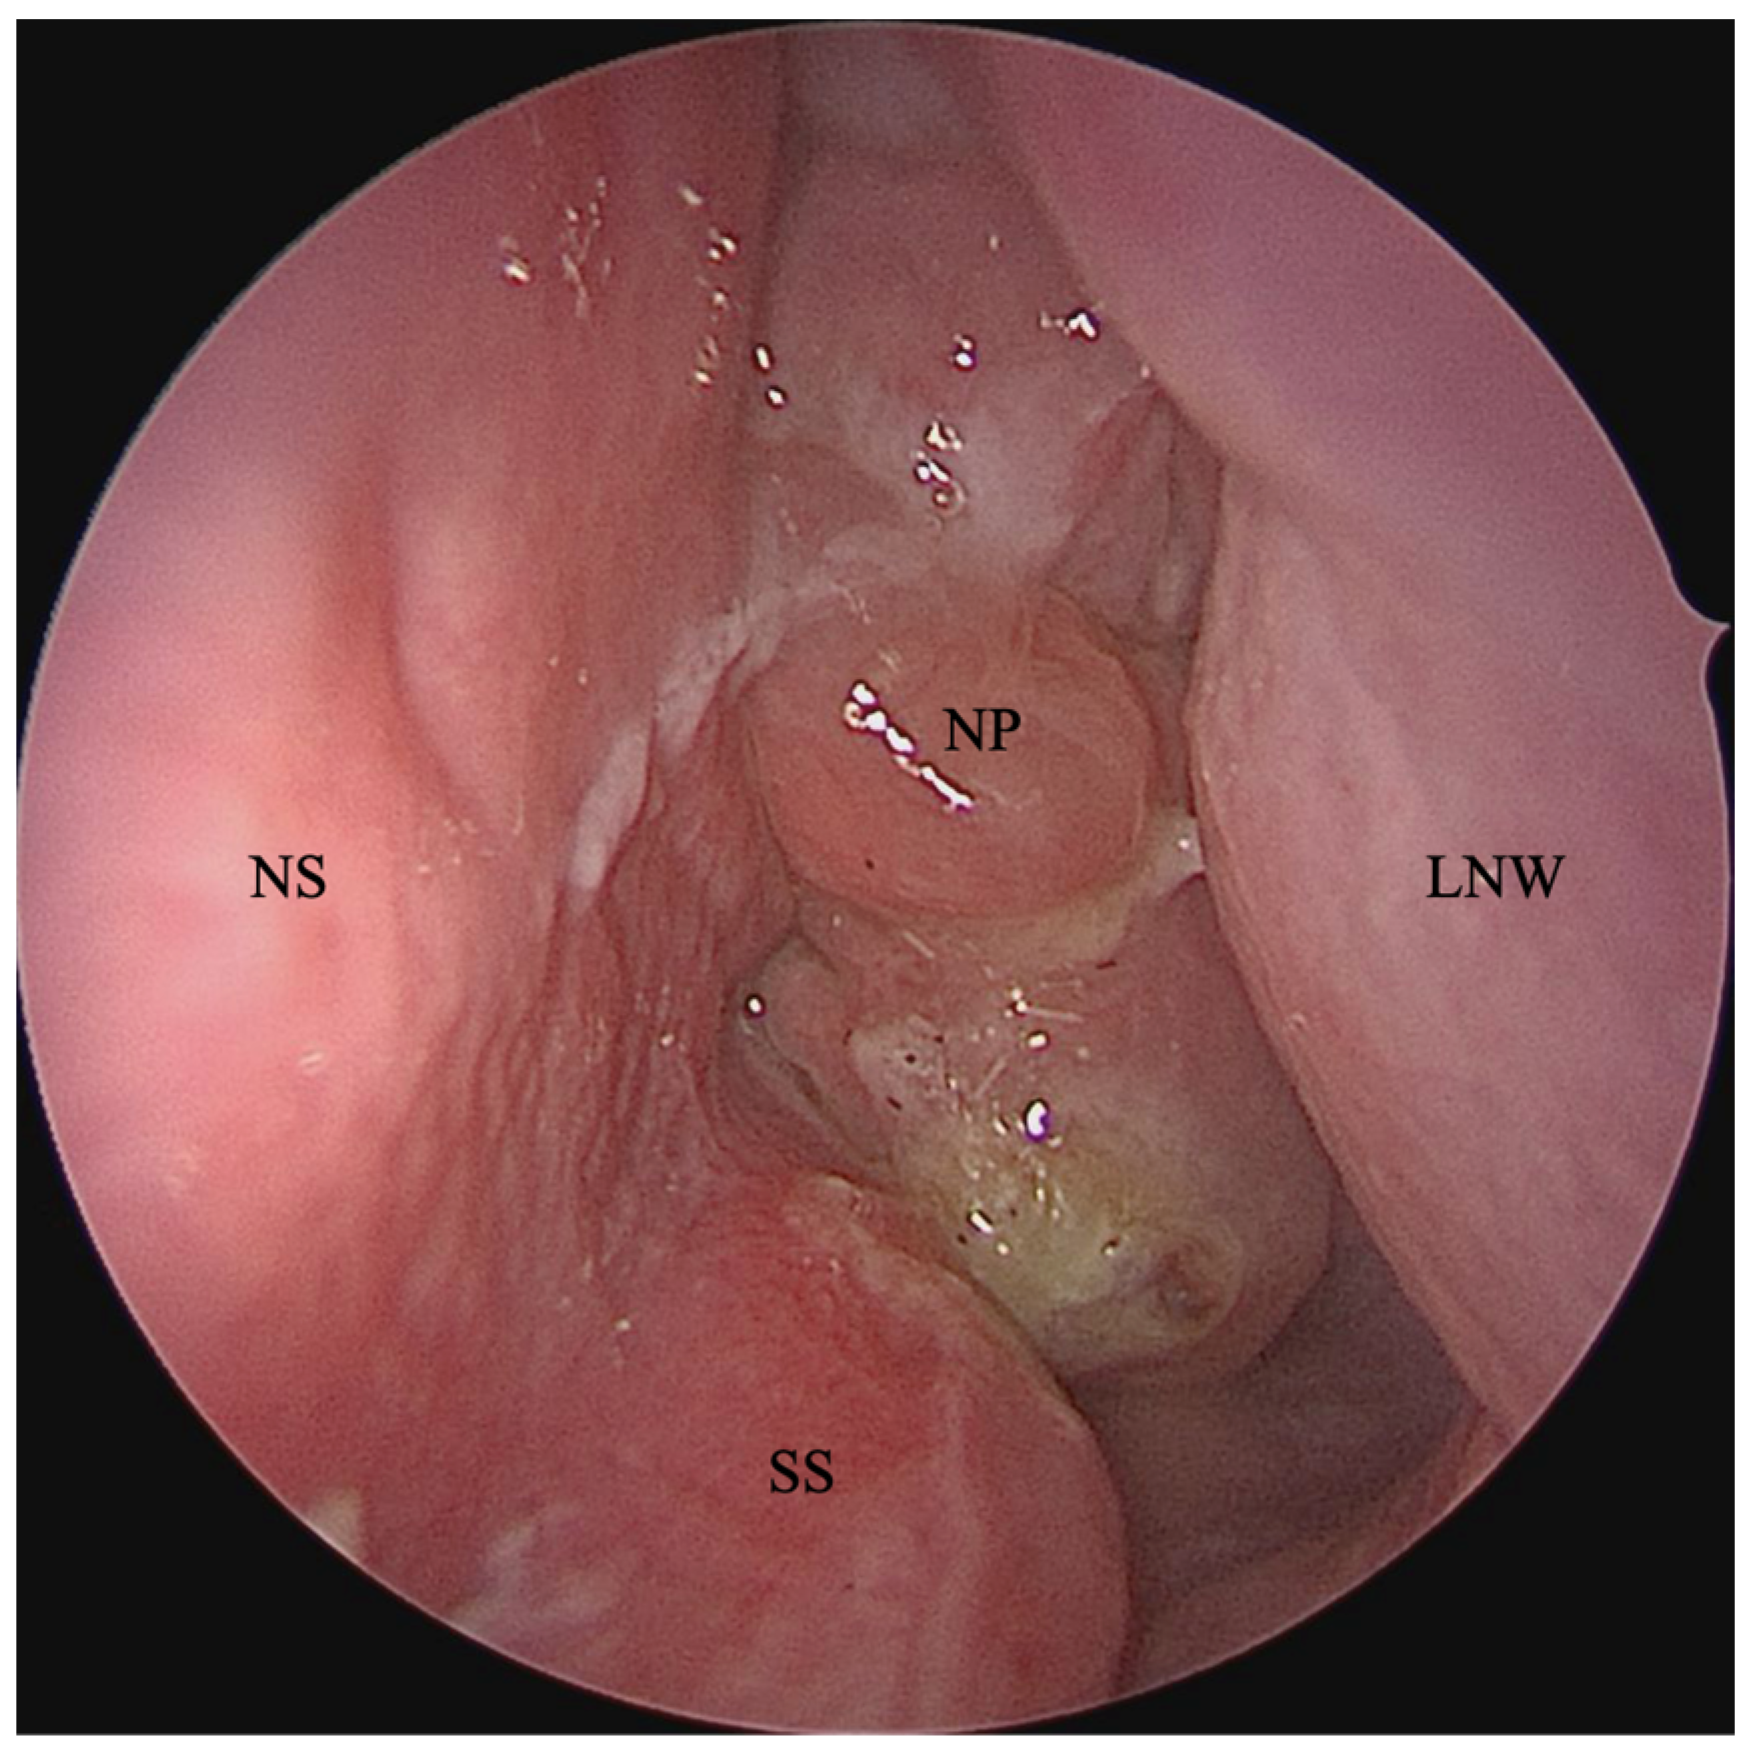

CRS is a heterogeneous process that consists of multiple phenotypes and endotypes. CRS with nasal polyposis (CRSwNP) is one of the main phenotypes of CRS and makes up approximately 30% of cases in non-CF individuals (Figure 1) [29]. CRSwNP in people without CF (Pw/oCF) typically presents between 40 and 60 years of age and is usually bilateral in nature [29,30]. The prevalence of nasal polyposis among adults with CF has been estimated at 32% to 44% [31,32,33,34], while the prevalence in pediatric patients is approximately 45% to 57% [3,35,36,37]. Additionally, the prevalence of CRSwNP among pediatric patients with CF increases with age—nasal polyposis has been diagnosed in 18% of patients younger than six years and 45% of adolescents [37]. Modest differences in prevalence rates across age are likely due to variation in sampling in different cohorts.

Figure 1.

Left nasal cavity endoscopy images from a person with chronic rhinosinusitis with nasal polyposis. Abbreviations: NS = nasal septum; SS = septal spur; NP = nasal polyps; LNW = lateral nasal wall.